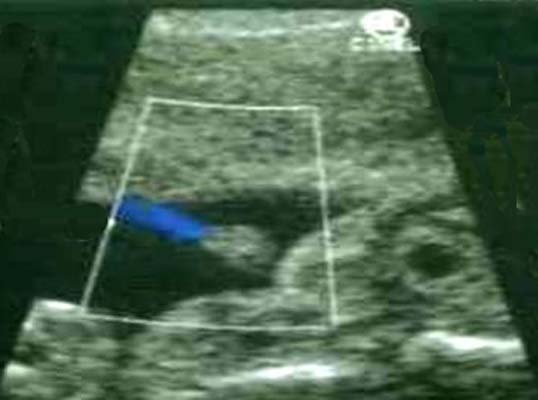

Flux urinaire - Au niveau urétral